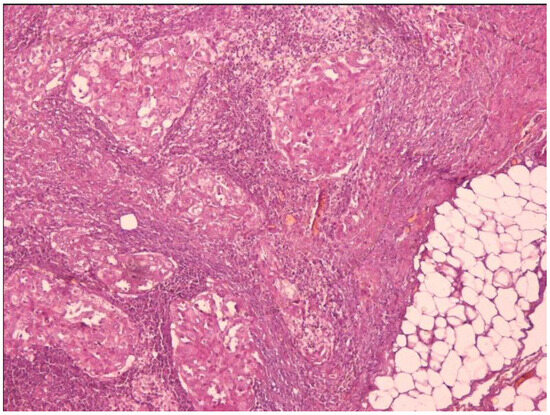

| PRESENT CASE | 1 | 1/0 | 45 | PDTC, hobnail, tall-cell | 1/1 | 1/1 (brain, bone, sinus) | 1/1 | TTmy (+neck dissection, completion ND) | 2 | Lenvatinib, sorafenib, trametinib/dabrafenib | DOD | BRAF |